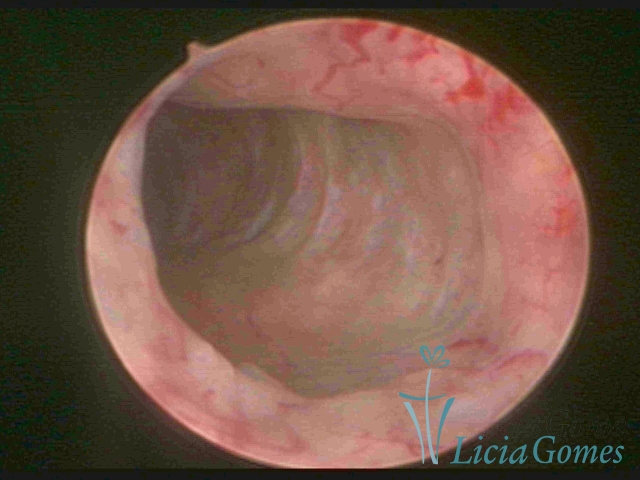

Unicornuate uterus

It presents a tubular cavity with an impaired intracavitary space, resembling the shape of a banana, whose the narrowest edge contains the tubal ostium. The endometrium is compatible with the menstrual cycle and the cervical canal is normal, in structure and trophism.